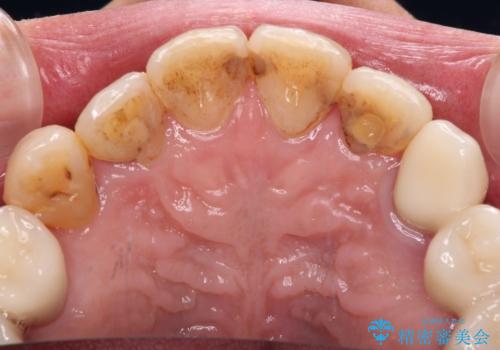

- 歯並びやグラグラする奥歯など、気になる所を全部治したいとのことで来院された患者様です。

奥歯は咬み合わせや歯周病により歯槽骨が失われていたり、むし歯や破折している歯などがあったりと、歯周病治療やインプラント補綴、矯正治療など、総合的に治療が必要と診断されました。

まずは歯周病治療やインプラント埋入を行い、環境が整った後にワイヤーを併用したインビザライン矯正を行い、オールセラミッククラウンにて補綴治療を行うこととしました。

治療中は仮歯が頻繁に脱落したり、歯周外科によりむき出しとなった歯根が知覚過敏を起こしたりと、苦労は絶えませんでしたが、4年の治療の後にスッキリと仕上げることができました。